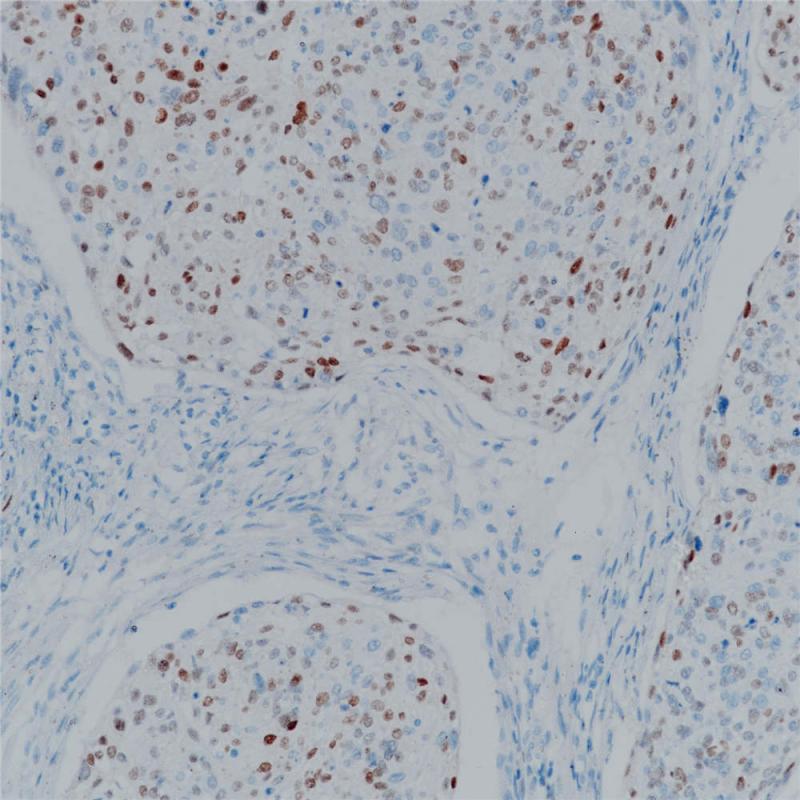

p21 重组兔单克隆抗体

p21是由位于6号染色体(6 p21.2)的CDKN1A基因编码的蛋白,也被称为细胞周期依赖性激酶抑制剂。p21与CDK2/CDK4结合的同时会抑制他们的活性,从而在G1期起调节细胞周期进程的作用。p21在所有成人组织中表达,在肿瘤组织中也有广泛地表达,例如胃癌、非小细胞肺癌、甲状腺癌。p21表达通常与预后良好相关。

阳性对照

宫颈癌

亚细胞定位

细胞核